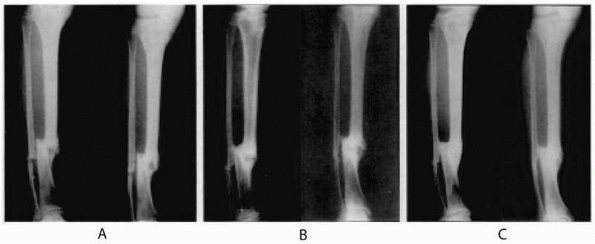

compression-distraction osteogenesis using the Ilizarov-type circular

external fixator. After an average of 30-month follow-up, results were

excellent in 21 and good in 3 patients. Functional assessment scores

were excellent in 19, good in 4, and fair in 1 patient (Fig. 5-5).

![]() |

|

FIGURE 5-5 A 53-year-old man sustained a grade IIIB open fracture of his left distal tibia with 8.5 cm of bone loss. A. Preoperative anteroposterior and lateral radiographs. B. Late postoperative radiographs taken at the end of the distraction period. C.

Radiographs after frame removal displaying complete union of the fracture and completed lengthening through the proximal tibia. D. Leg length equality at the end of treatment. E,F. Ankle range of motion during the last follow-up examination. (Reprinted with permission from Sen C, Kocaoglu M, Levent E, et al. Bifocal compression-distraction in the acute treatment of grade III open tibia fractures with bone and soft-tissue loss-a report of 24 cases. J Orthop Trauma 2004;18:150-157.) |